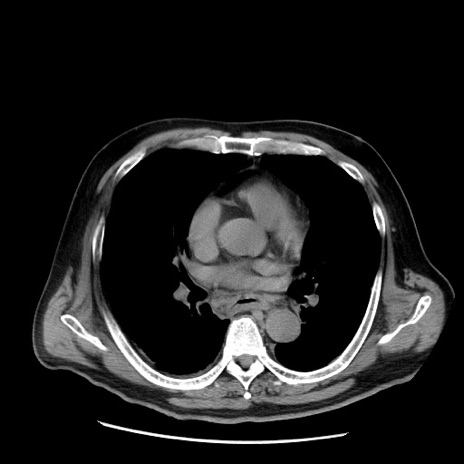

症例20(横断像)

【症例】 60歳代男性

【主訴】 腹部膨満、嘔吐

【現病歴】5日前頃より倦怠感を認め食事量減少し4日前の朝嘔吐、食事摂取困難となった。 3日前近医受診し点滴施行され整腸剤などを処方された。 当日他院を受診し、腹部膨満著明、炎症反応の上昇(CRP10.8、WBC11200)あり、紹介受診となる。

【身体所見】 意識JCS1 受け答えがはっきりしないBP 111/57mHg、 P 67bpm、、BT35.2°C、SpO2 97%(RA)、 腹部:膨隆、打診で鼓音あり、全体的に圧痛有り、腸蠕動音(-)、反跳痛ははっきりせず。

【データ】WBC 11400、CRP 14.20